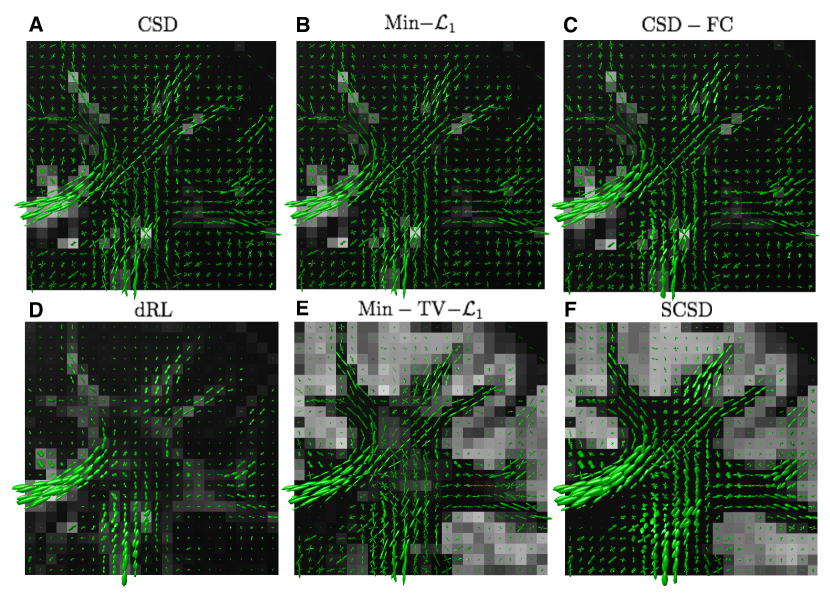

Fig. 10 depicts the reconstructions of fODFs obtained using the CSD (Subplot A), Min- (Subplot B), CSD-FC (Subplot C), dRL (Subplot D), Min-TV- (Subplot E), and SCSD (Subplot F) for the axial view and s/mm2. As opposed to Subplots A3-4 and B3-4 in Fig. 9, the fODFs in Fig. 10 are shown superimposed over the values of their corresponding IDMs. Analysing these results reveals the principal drawback of SD methods which disregard the effect of isotropic diffusion. In particular, not only CSD and Min- but also CSD-FC tend to yield spurious estimates of fODFs in anatomical regions corresponding to the cortical grey matter – the result which stands at odds with the fact that these regions are known to be devoid of neural fibre bundles. Further, although being capable of coping with the presence of isotropic diffusion, the dRL algorithm is “blending” and , which effectively impairs the angular resolution, and therefore the resolvability of crossing fibre tracts. Moreover, neither of the aforementioned methods has been found to be capable of reliably recovering the IDMs. At the same time, both Min-TV- and SCSD yield anatomically consistent reconstructions of the IDMs, with much less noisy results obtained in the case of SCSD. (This point is further illustrated by Fig. 11 which shows the “zoomed-out” IDMs recovered by the SD methods under comparison for the case of s/mm2.) Moreover, a closer inspection of Fig. 10 reveals that the fODFs estimated by means of SCSD are characterized by a smoother and more consistent spatial variability (owing to the fibre continuity constraint), thereby exhibiting a better adherence to the expected connectivity within an in vivo brain.

The reconstructions obtained for the same axial view and s/mm2 are depicted in Fig. 12, whose composition is identical to that of Fig. 10. Although fairly close in appearance to the previous case, these reconstructions allow us to make a number of important observations. First of all, as compared to the case of s/mm2, a wider bandwidth of the HARDI signals at s/mm2 leads to a better angular resolution, which is particularly noticeable in the case of dRL. Moreover, despite considerably worse noise conditions, the fODF reconstructions obtained by means of Min-TV- and SCSD have much less residual noise over the areas occupied by cortical grey matter, where isotropic diffusion is expected to prevail. This fact indicates the effectiveness of the regularization schemes exploited by these SD methods. Finally, a closer inspection of the glyphs in Fig. 12 reveals that the fODF reconstructions yielded by SCSD demonstrate a better spatial smoothness and anatomical consistency. The same observations can be made in the case of the coronal view, as shown in Figs. 13 and 14 for s/mm2 and s/mm2, respectively. (Note that the local region represented by these figures has been chosen according to the results in [44], which also provides indication of specific fibre bundles within the selected regions of interest).